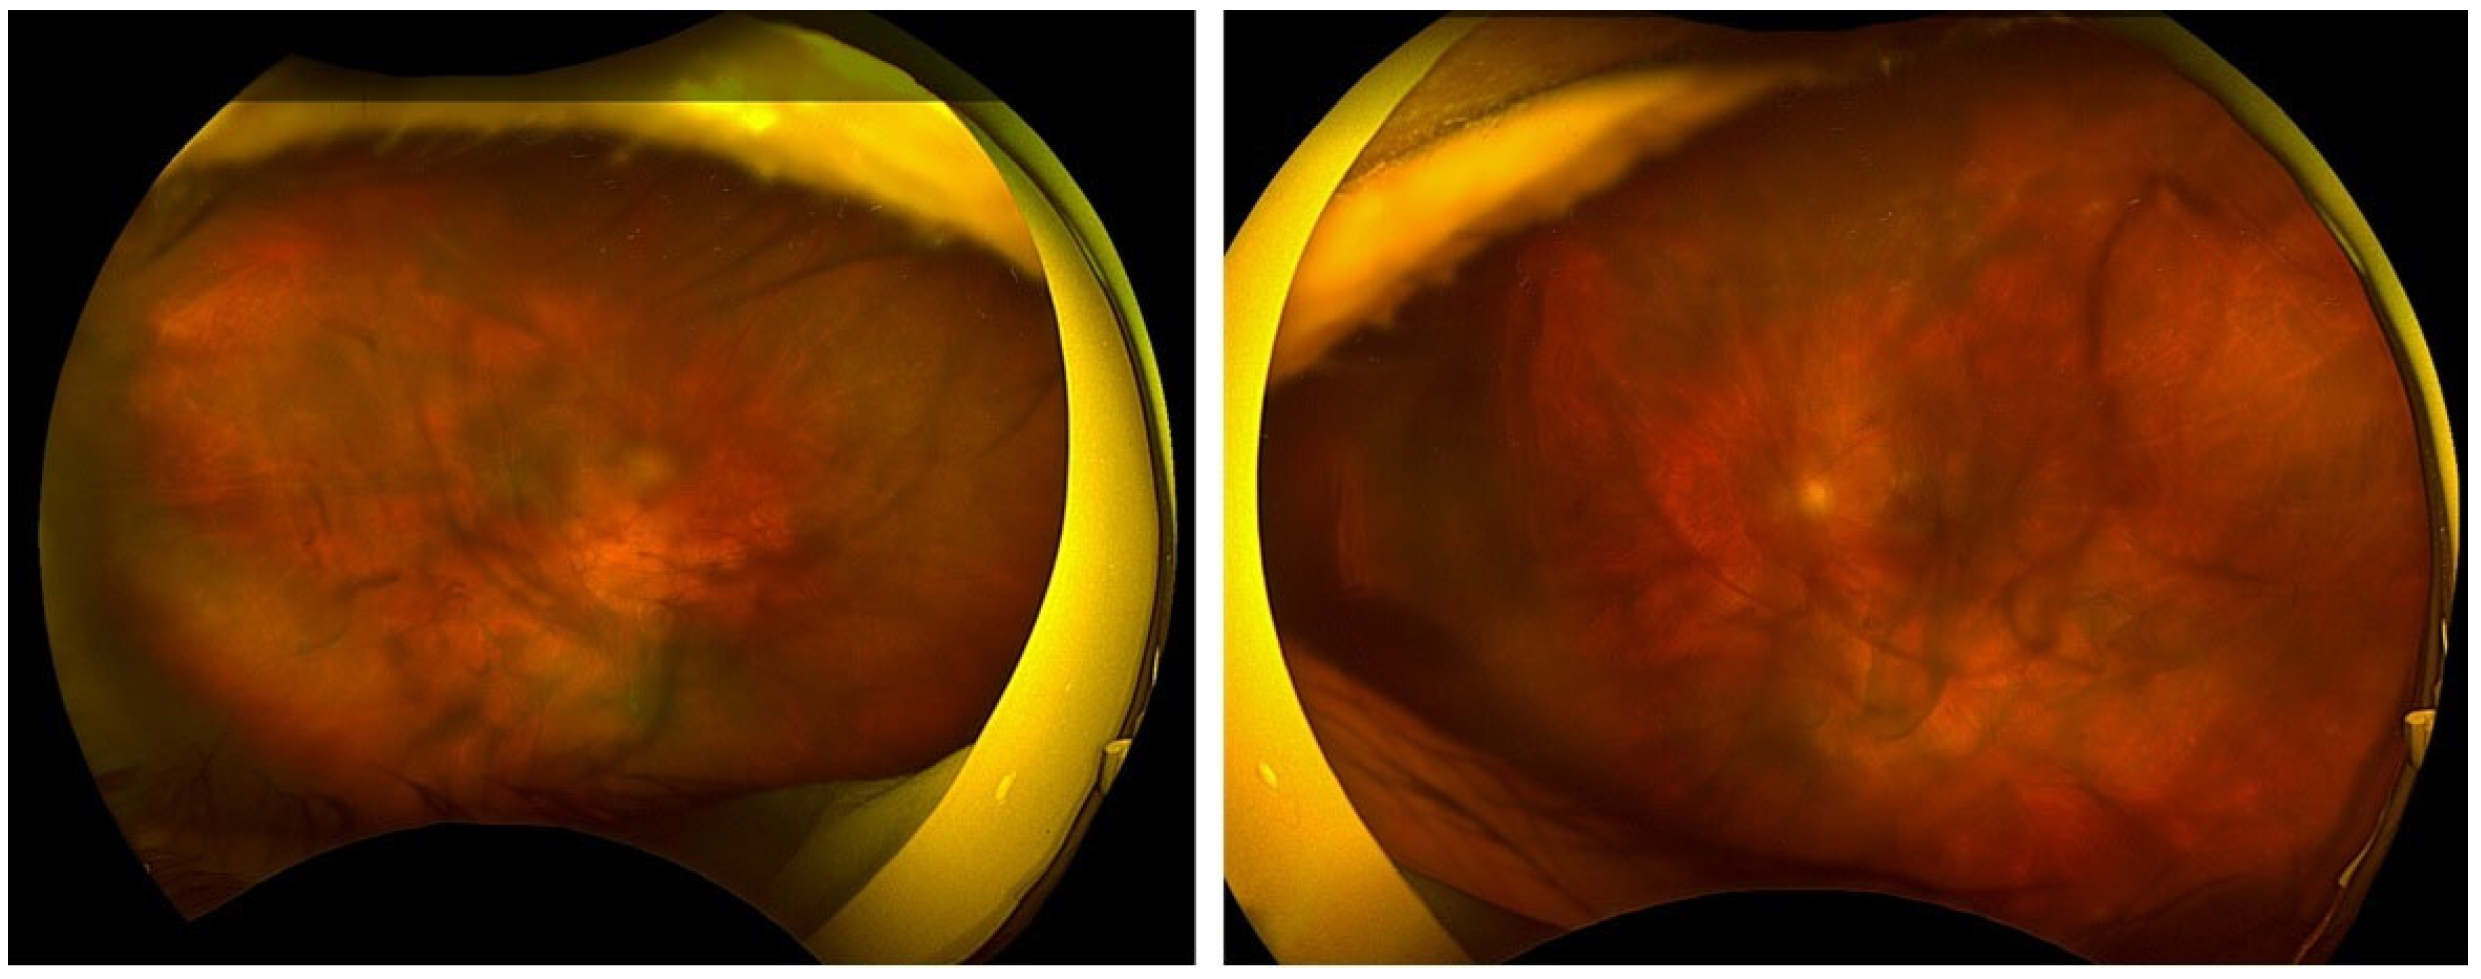

2. Case Report